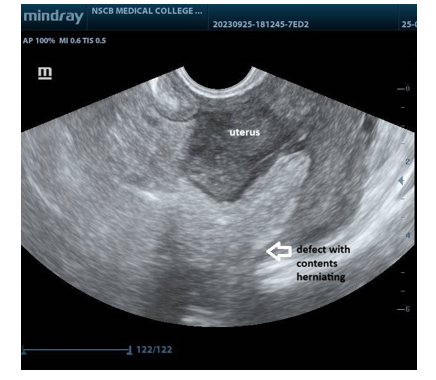

The patient was sent to our department for screening ultrasonogram of the pelvis. On TAS, the uterus was normal in size, with a 10 mm sized rent at the fundus region of the uterus, which extended through and through the myometrial plane into the serosal layer abutting the endometrial cavity, through which echogenic content was seen herniating. On transvaginal ultrasound, bowel loops and mesentery were seen herniating into the defect. There was minimal intra peritoneal collection noted in the cul-de-sac.

In our case, the patient has bowel loops and mesenteric fat herniating into the uterine perforation at the fundus region of the uterus This could be attributed to her parity and repeated evacuation of the uterine cavity. In a meta analysis done by ZorilÄ? et al(3), uterine perforation is common in the fundus region, which allows the omentum and other abdominal organs to enter the uterine cavity. Myometrial characteristics, such as contractility, can explain the absorption of the omentum or intestines, even if ultrasound shows only the perforation site and an empty cavity after the procedure.

Figure 1: Shows the omental and intestinal contents herniating into the uterine myometrium just abutting the endometrium